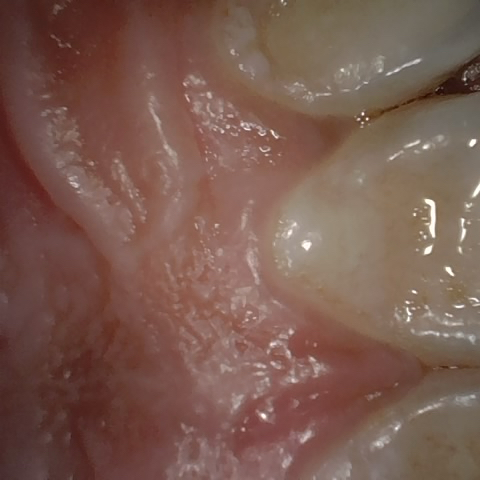

Annotated as "Good"